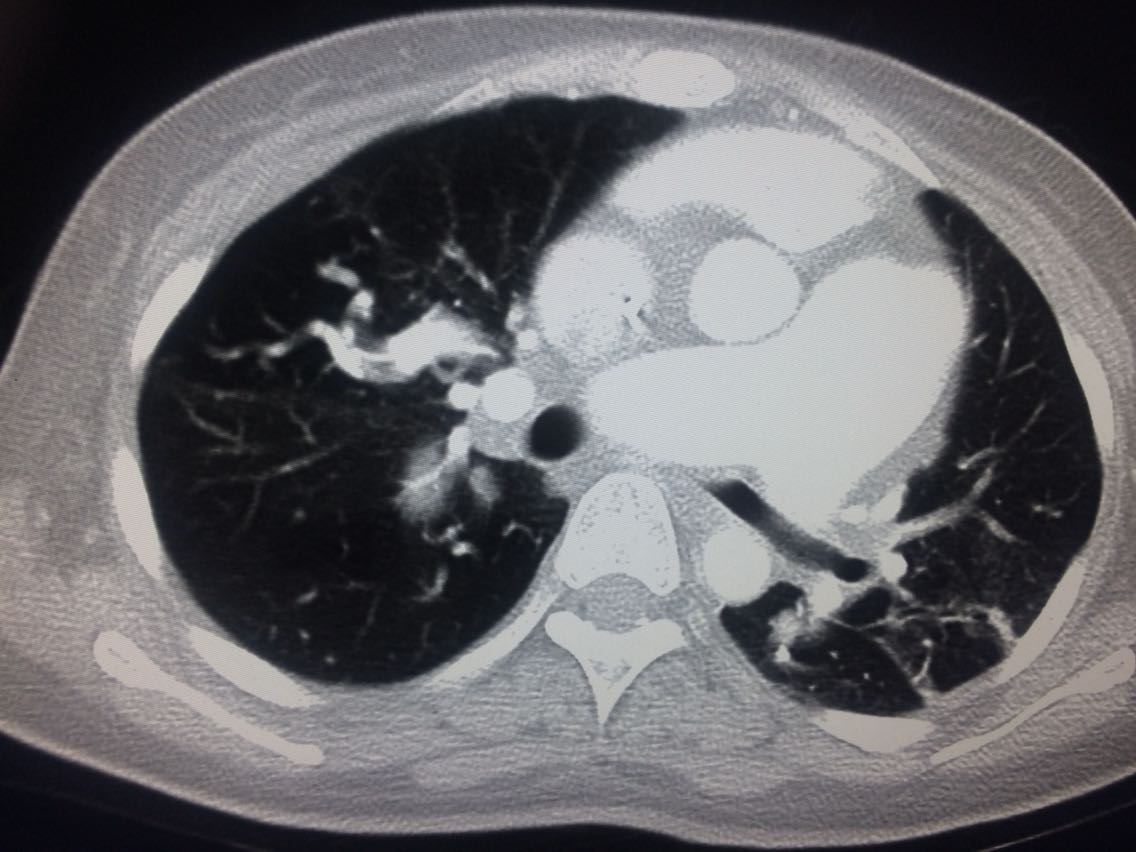

诊断,肺动脉高压。 鉴别诊断,肺动脉栓塞。 影像诊断,肺动脉高压,肺门区出现残根征,肺动脉扩张,肺动脉段膨隆,心影增大。CTA见迂曲增宽的肺动脉。 肺栓塞,影像可见典型充型缺损影,伴随肺纹理的减少。 治疗以对症处理为主,病人病史14年。 讨论诊断和鉴别诊断? 随访,症状好转。